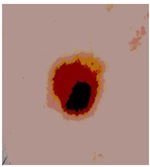

![]() | ![]() | ![]() | ![]() |

| Img1 | --- Pixel Intensity (0–255) ---> | ||

| Img2 | --- Pixel Intensity (0–255) ---> | ||

| Img3 | --- Pixel Intensity (0–255) ---> | ||

| Img4 | --- Pixel Intensity (0–255) ---> | ||

| Img5 | --- Pixel Intensity (0–255) ---> | ||

| Img6 | --- Pixel Intensity (0–255) ---> | ||

| Img7 | --- Pixel Intensity (0–255) ---> | ||

| Img8 | --- Pixel Intensity (0–255) ---> | ||

| Img9 | --- Pixel Intensity (0–255) ---> | ||

| Img10 | --- Pixel Intensity (0–255) ---> | ||